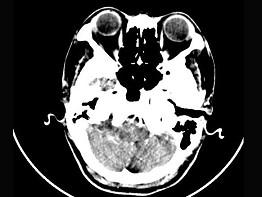

女,45岁,右耳听力下降半年余,CT检查如图,最可能诊断为 ( )

• A.脑膜瘤

• B.继发性胆脂瘤

• C.三叉神经瘤

• D.原发性胆脂瘤

• E.听神经瘤

答案: E